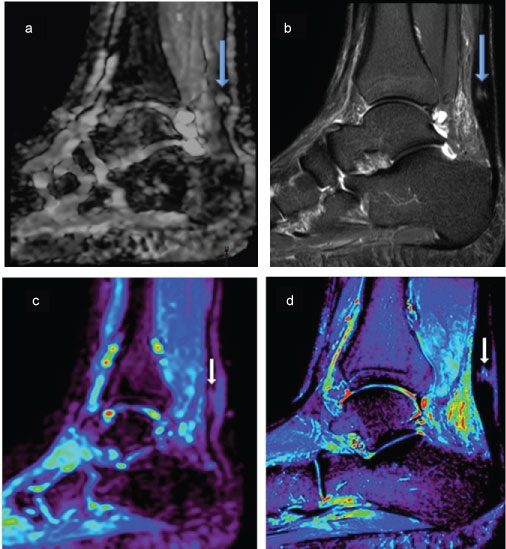

Qualitative findings for all AT pathologies on both routine MRI and DWI were correlated (Figure 3). DWI demonstrated a 61.7% sensitivity and 96.3% specificity (p = 0.001) for pathology detection relative to routine scan MRI findings with PPV of 96% and NPV of 59%. Similarly, ADC images were correlated and showed 90.2% sensitivity, and 85.1% specificity for detection of pathology relative to routine MR findings, with PPV of 90.2% and NPV of 69.6%, and p = 0.001. A "Type III Tests of Fixed Effectsa" of significance was applied to the ADC values and a significant difference in the ability to differentiate the type of AT pathology p 0.001 < 0.05 was noted (Table 5). However, when correlating ADC with the time point of the initial and follow-up scans, or the side of injury (left/right AT), values were not significantly different, p values were respectively p 0.802 > 0.05, p 0.334 > 0.05.

Figure 3: Figure of two different patients top and bottom, Top Images (a) Sagittal DW; (b) STIR, both images are of the same pathology (big arrows) partial tear of the AT, the images display qualitative approach to pathological findings. Bottom images; (c) ADC map; (d) STIR images, these are of the same patient (small arrows) showing a micro tear of the Achilles tendon the ADC maps were used for Qualitative values of the pathology using the ROI method, once corelated with STIR images. View Figure 3